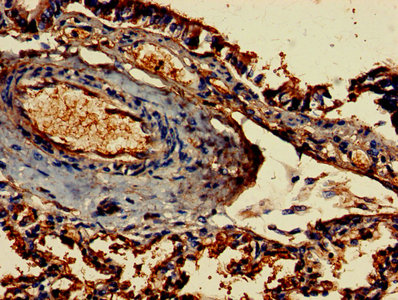

圖片:

應用范圍:ELISA, IHC, IF

Application Recommended Dilution IHC 1:20-1:200 IF 1:50-1:200 -